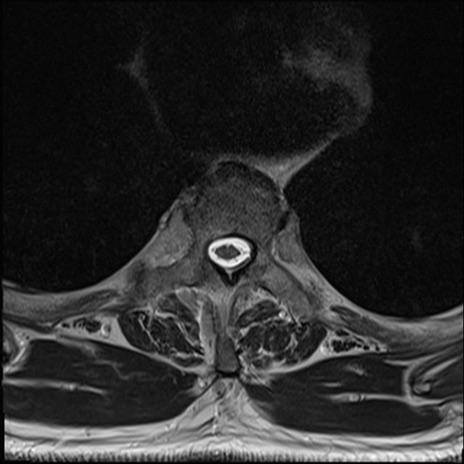

【整形】TIPS症例7 頚椎MRI T2WI(横断像)

頚椎MRI

矢状断像と横断像